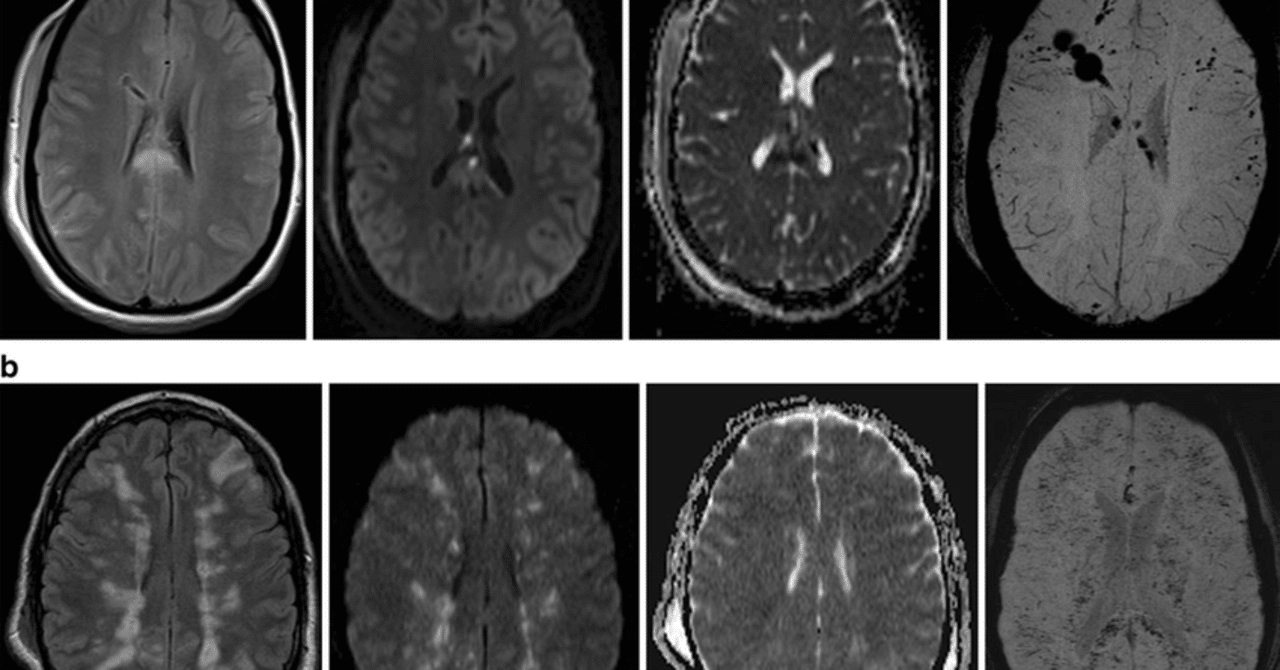

FESを明確に診断できる単一の検査はありません。脂肪塞栓の存在にもかかわらず、画像検査では正常に見える場合があります。そのため、医師は通常、身体検査、病歴(最近の骨折歴を考慮)、およびガード基準として知られるものに依存します。